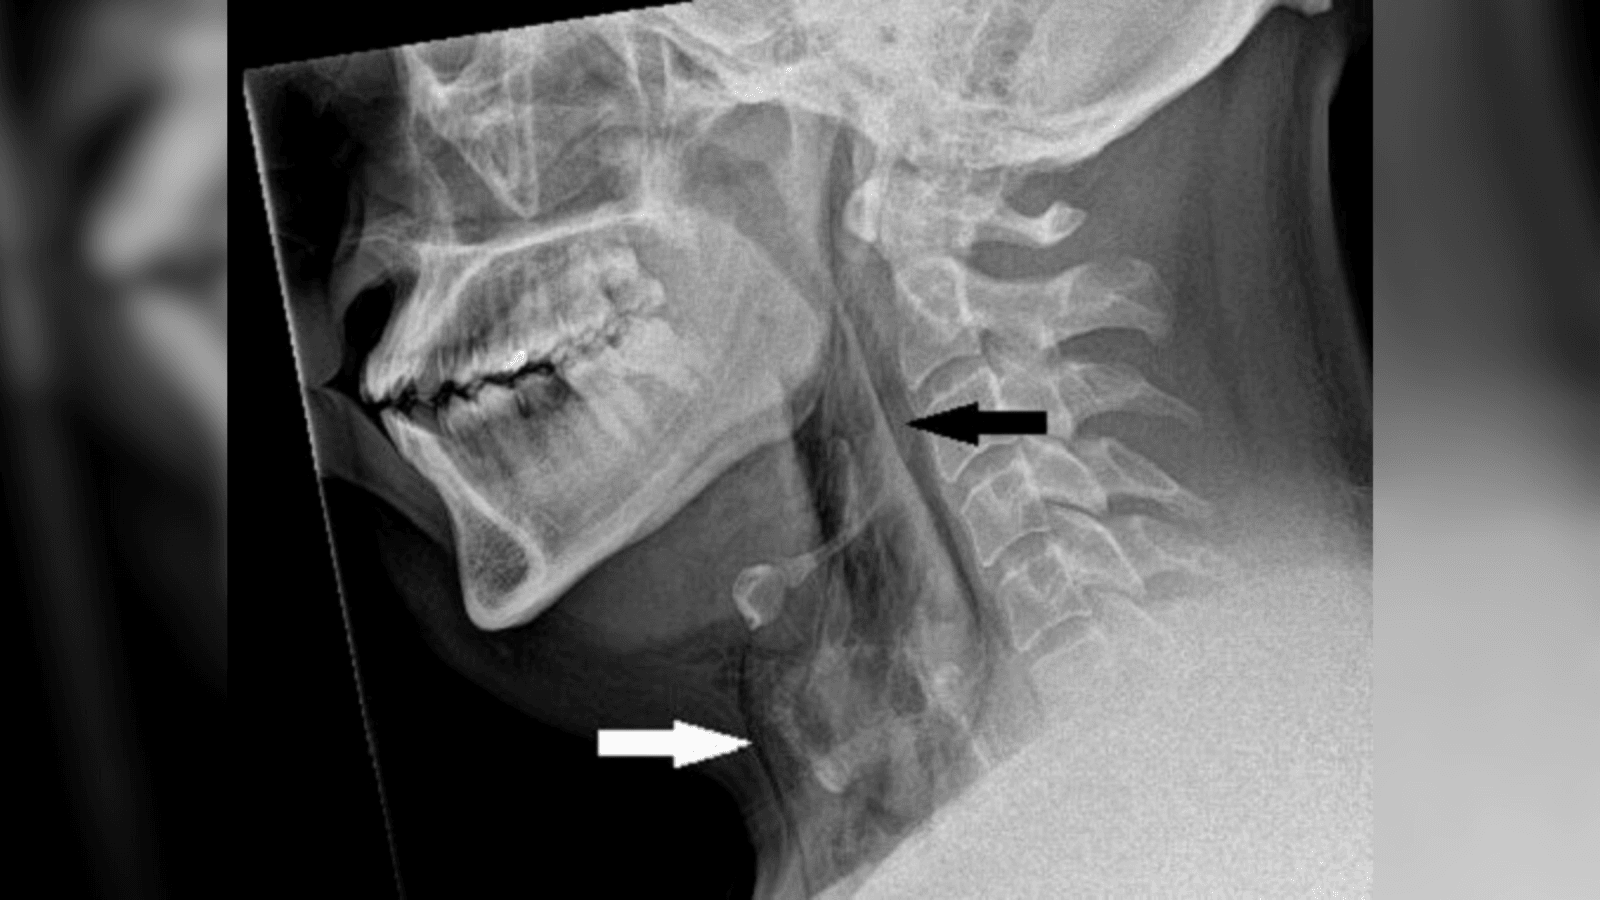

Prześwietlenie szyi wykazało, że pacjent cierpiał na odmę, czyli rozedmę podskórną. Jest to stan, kiedy w tkance podskórnej znajdują się pęcherze powietrza – zwykle ma to miejsce w klatce piersiowej, szyi lub twarzy. Leczenie odmy zazwyczaj nie jest konieczne, gdyż powietrze samoistnie się wchłania. Tomografia komputerowa (CT) wykazała, że rozdarcie znajdowało się między kręgami szyjnymi.